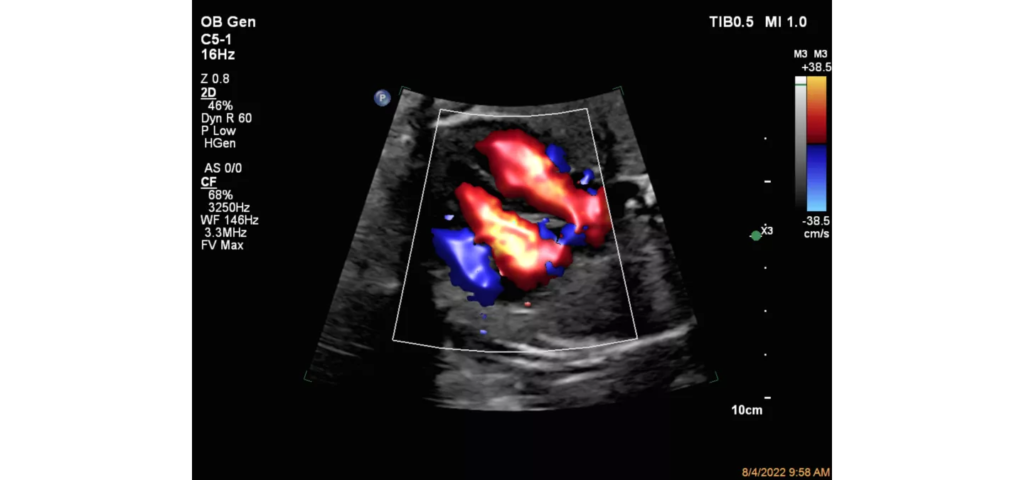

Philips EPIQ Elite ultrasound features an exceptional level of clinical performance, workflow, and advanced intelligence to meet the challenges of today’s most demanding practices. The EPIQ Elite platform brings ultimate solutions to ultrasound, with clinically tailored tools designed to elevate diagnostic confidence to new levels.